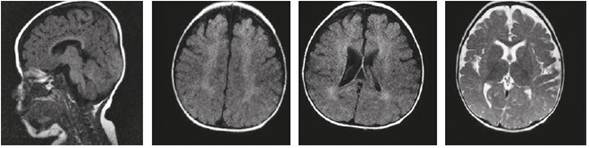

Las imágenes cerebrales, analizadas por un segundo neurorradiólogo, fueron informadas como sugestivas de noxa perinatal de posible origen hipóxico-isquémico; en los controles siguientes no se evidenció progresión de las lesiones, ni aparición de un patrón sugestivo de alguna de las leucodistrofias de origen metabólico (Figuras 1 y 2). La espectroscopia por RMC fue normal (Figura 3).